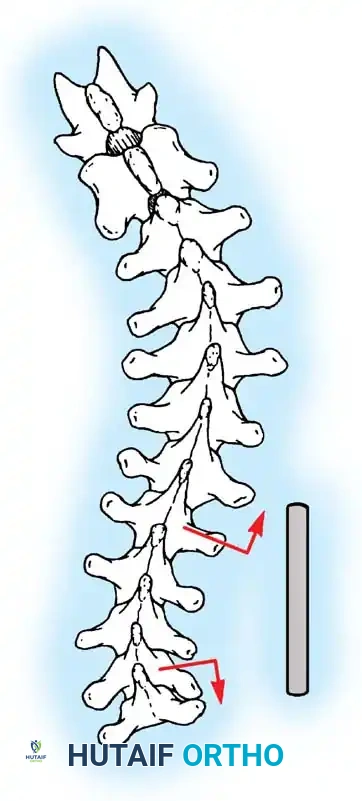

The Moe Technique (Thoracic Spine)

The Moe technique is a highly effective method for achieving intra-articular arthrodesis in the coronally oriented thoracic facet joints.

Fig. 38-26: The Moe technique of thoracic facet fusion, demonstrating the creation of hinged bone flaps.

- Expose the spine fully to the tips of the transverse processes.

- Using a sharp osteotome or Cobb gouge, begin a cut over the cephalad articular process at the base of the lamina.

- Carry this cut along the transverse process almost to its tip. Bend this cortical fragment laterally so it lies between the transverse processes, ideally leaving it hinged on its lateral periosteal attachment to preserve local vascularity.

- Thoroughly denude all articular cartilage from the superior articular process using a sharp curet.

- Make a secondary cut in the superior articular facet, working medially to laterally, producing another hinged fragment.

- Pack the resulting intra-articular defect tightly with cancellous bone graft.